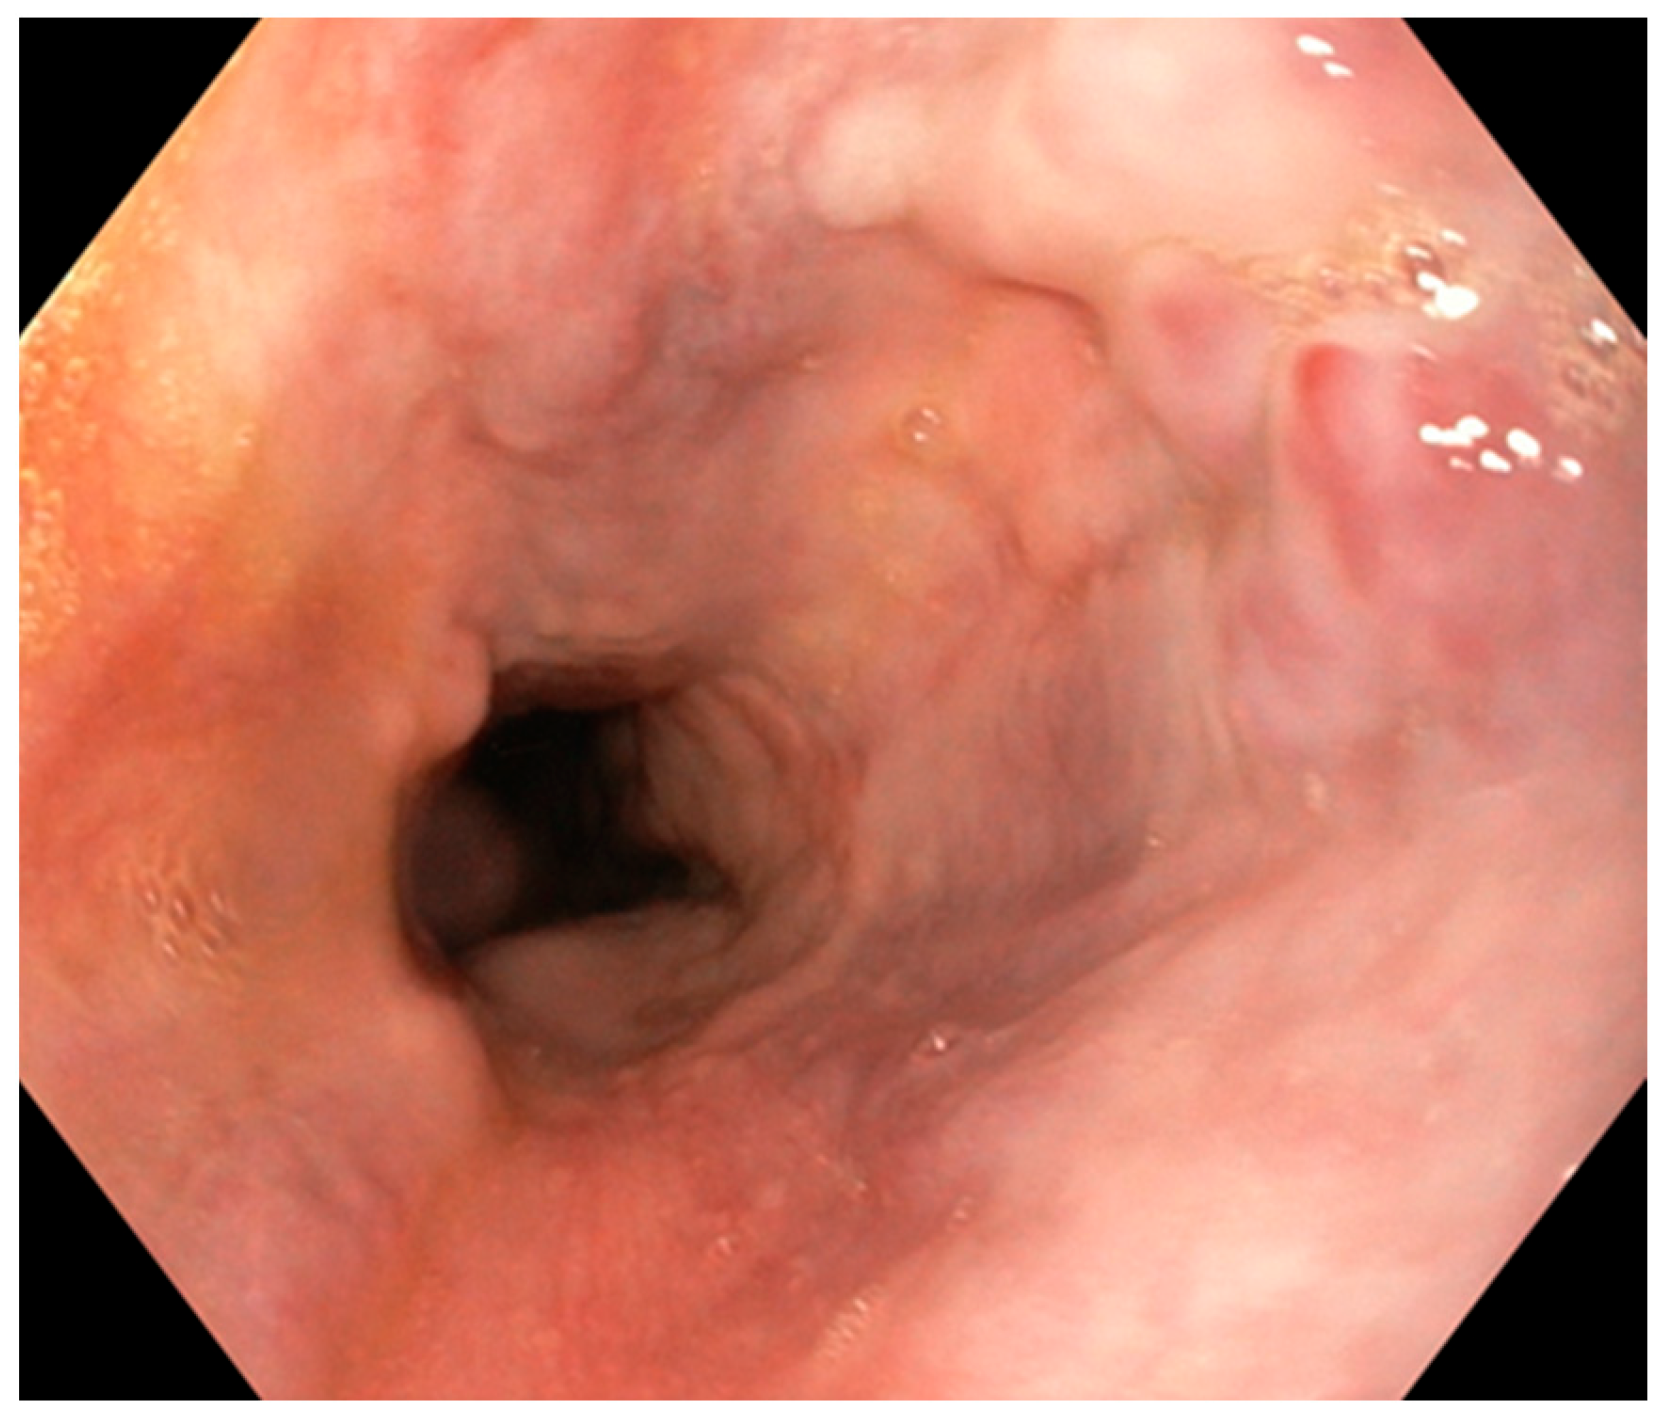

2. Case Report